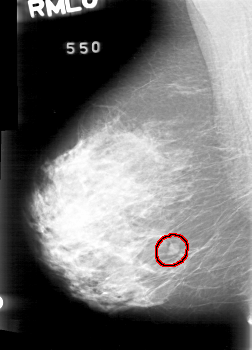

D_4022_1.RIGHT_MLO

RIGHT_MLO LINES 5236 PIXELS_PER_LINE 3766 BITS_PER_PIXEL 12 RESOLUTION 43.5 OVERLAY

FILE: D_4022_1.RIGHT_MLO.OVERLAY

TOTAL_ABNORMALITIES 1

ABNORMALITY 1

LESION_TYPE MASS SHAPE ROUND MARGINS OBSCURED

ASSESSMENT 0

SUBTLETY 5

PATHOLOGY BENIGN

TOTAL_OUTLINES 1

BOUNDARY